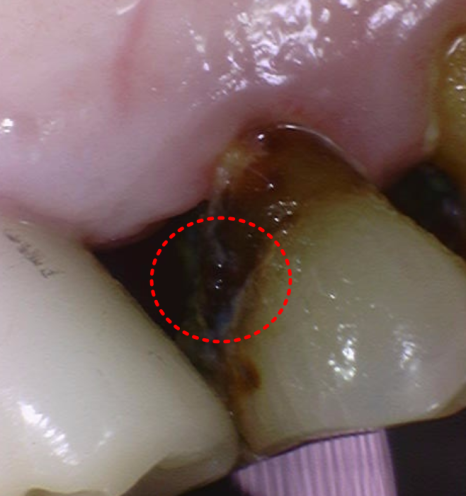

입안을 살펴보니,

#12(오른쪽 앞니) 부위에

치아 사이로 충치가 진행돼 있었습니다.

231109

위 앞니(#11~22)는 브릿지 주변 잇몸에

염증이 꽤 심했고,

고름(배농)이 동반되는 상태였습니다.

이 상태로는 치아를 오래

쓰지 못할 것으로 보였죠.